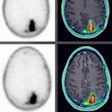

Is this the Best Radiology Image of 2014?